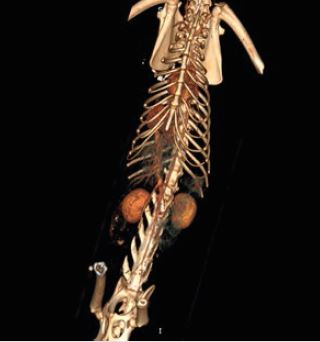

Global Illumination - це нова революційна технологія 3D/4D рендерингу, яка допомагає створити більш фотореалістичне зображення анатомії. Редагуйте, сегментуйте та фіксуйте фотореалістичні

зображення для покращення лікування пацієнтів та передопераційного планування.